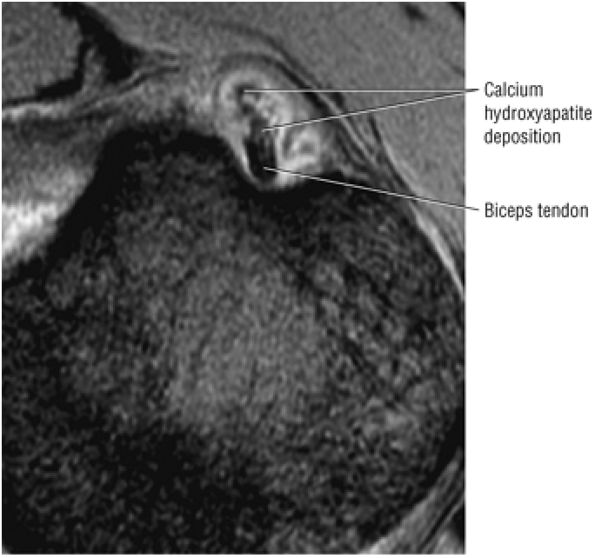

T2* GRE images (10-cm FOV) are used to evaluate intralabral pathology, subscapularis tendinosis, and calcific tendinitis (Fig. 8.3).